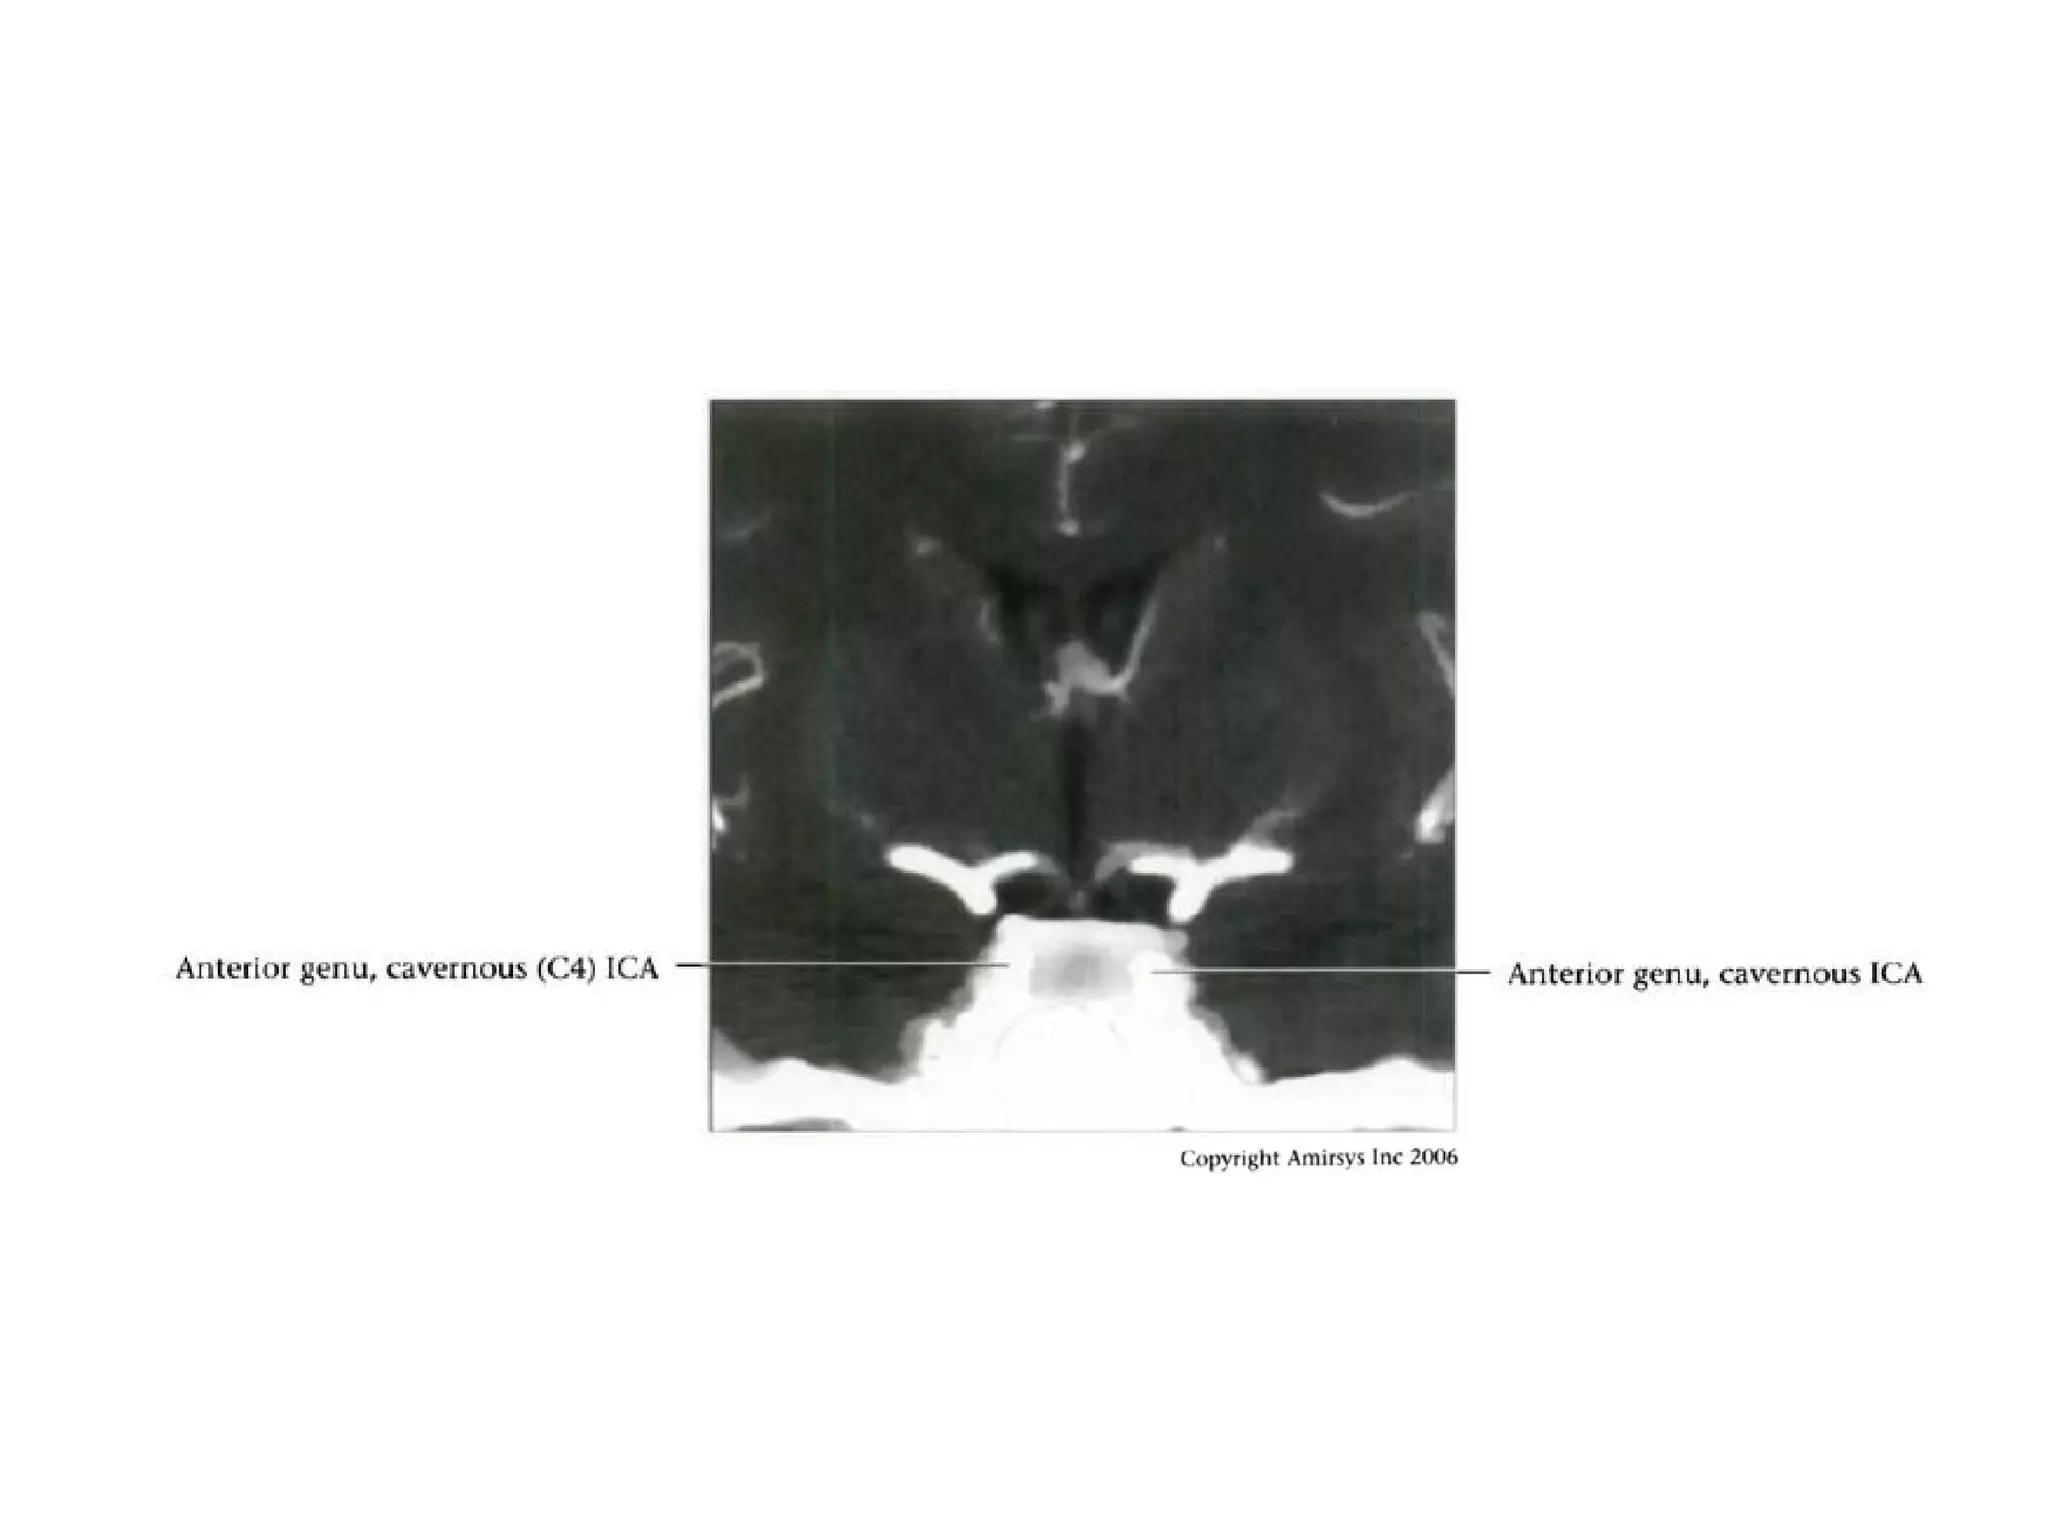

Cavernous (C4) segment

• Three subsegments joined by two genus (knees)

- Posterior vertical (ascending) portion

- Posterior (more medial) genu

- Horizontal segment

- Anterior (more lateral) genu

- Anterior vertical (subclinoid) segment

• Covered by trigeminal ganglion posteriorly

• Abducens nerve (CN6) is inferolateral

• Major branches

- Meningohypophyseal trunk (arises from posterior

genu, supplies pituitary, tentorium and clival dura)

- Inferolateral trunk arises from horizontal segment,

supplies cavernous sinus (CS) dura / cranial nerves;

anastomoses with ECA branches through foramens

rotundum, spinosum, ovale